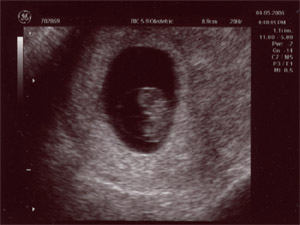

| May 2, 2006 - Twelve Week Ultrasound |

| Today was our

diagnostic ultrasound at the hospital. We got to see the baby dancing

all over the place. It was just so incredible. The technician

said that everything looked great and we were so happy to be able to see our

little bundle of joy. This was my second time seeing the baby on the

ultrasound, but this was Chris' first. He was so thrilled to see Baby

Palermo! ~Jen |